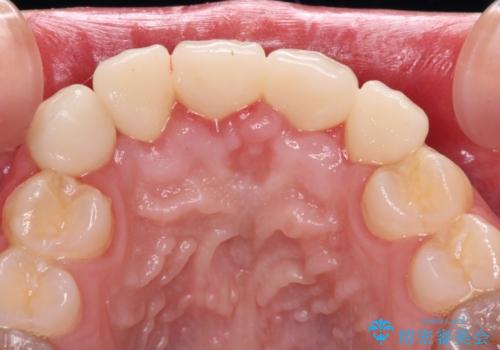

オールセラミッククラウン装着後、レントゲン写真より精度良く装着されていることは確認できているので、日頃のブラッシングで改善させるよう指導しています。